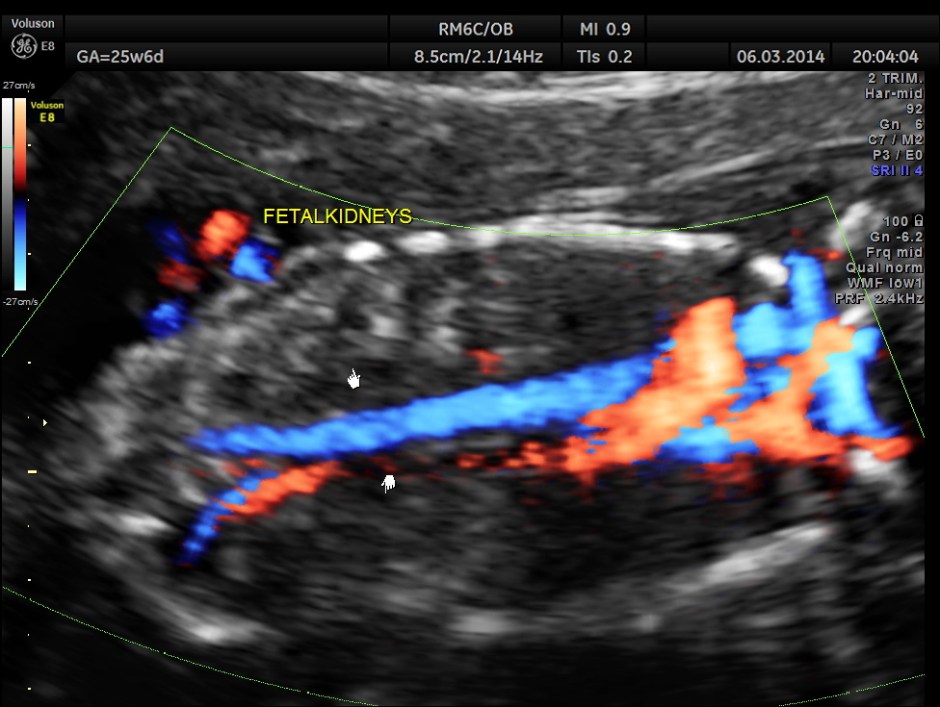

Fetal kidneys are hyperechoic and enlarged.